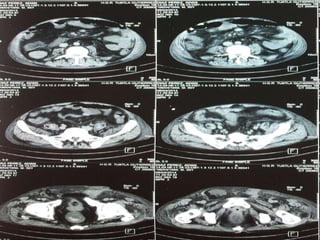

Anomalías Genitourinarias

11% de los pacientes pueden presentar estenosis

pieloureteral y/o hidronefrosis.